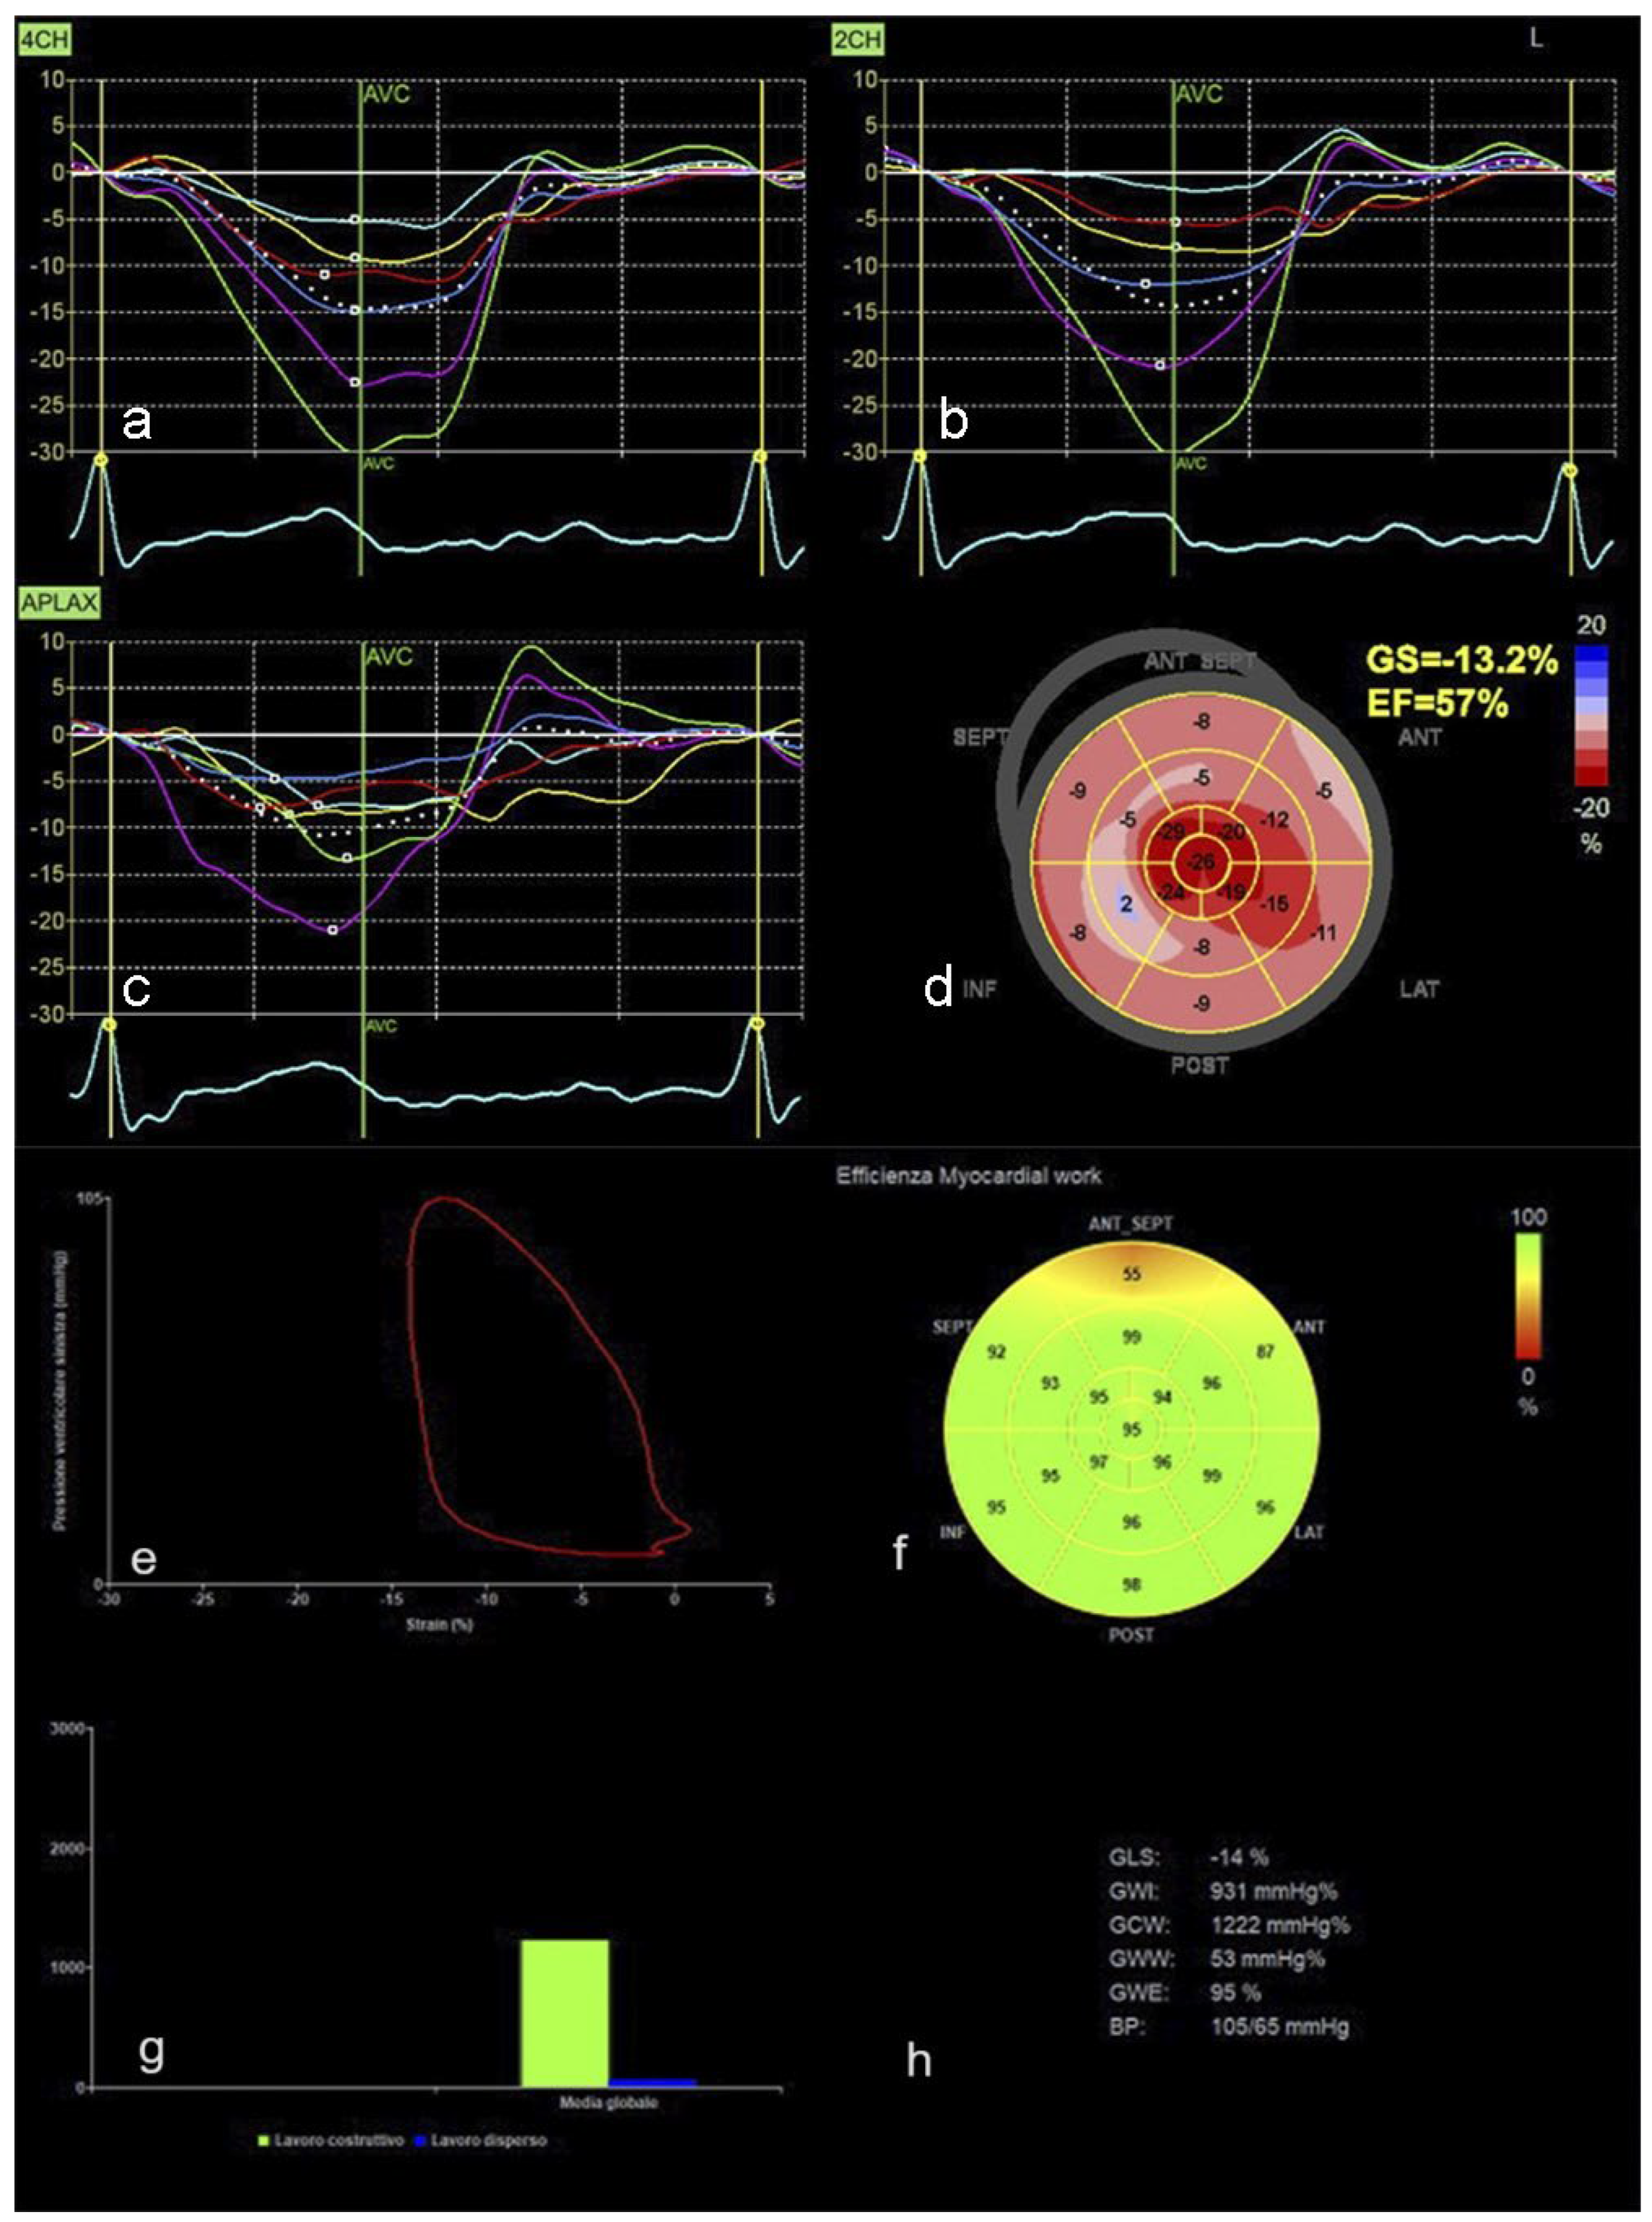

Cardiac Imaging Evolution: Artificial Intelligence-Guided Advancement